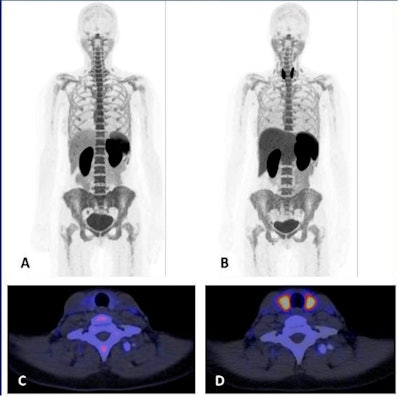

The researchers enrolled eight patients with confirmed metastatic melanoma. Patients underwent whole-body F-18 BMS986192 scans with a PET/CT scanner (Biograph mCT64 or mCT40, Siemens Healthineers) before and six weeks after starting ICI therapy.

The highest uptake of the tracer was seen in the spleen, bone marrow, kidneys, and liver. Tracer uptake in tumor lesions was heterogeneous. In total, 42 tumor lesions were identified in patients at baseline, with most lesions in the lungs (n = 21) and brain (n = 14). Tracer uptake was similar between tumor locations.

The researchers found F-18 BMS986192 uptake in lesions at baseline was negatively correlated with the change in the size of tumors at six weeks. Receiver operating characteristic (ROC) analysis demonstrated that F-18 BMS986192 uptake can discriminate between responding and nonresponding lesions with an area under the curve of 0.82.

"We found heterogeneous uptake of F-18 BMS986192 in metastatic lesions at all locations, which is in line with a heterogeneous response to immune checkpoint inhibitor therapy that is often observed in melanoma patients," the researchers wrote.